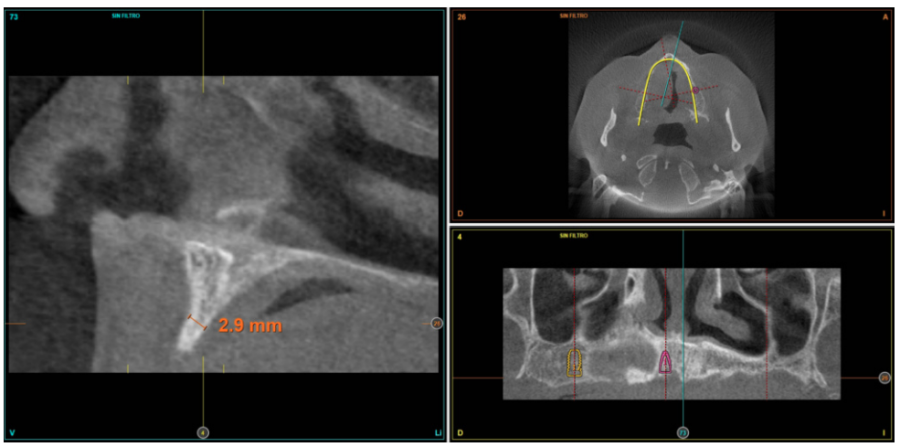

Posteriormente, se procede a la realización de un Cone-beam dental que ofrece una visión más exacta del tipo de rehabilitación implantológica que se pueda plantear. En los cortes correspondientes al maxilar superior, se observan zonas donde puede realizarse la inserción directa de los implantes como las correspondientes a 16 y la zona del incisivo central de este cuadrante (Figuras 4-5) o en el segundo cuadrante el área de 27. En cambio, en la zona correspondiente a los dientes 21 y 23 existe una atrofia horizontal importante, con una anchura ósea residual de aproximadamente 3,5 mm en la zona media de la cresta, con una ampliación en el área más basal de la misma y conservación de ambas corticales. Esto hace que se opte por una técnica de Split de cresta, en este caso en dos fases para poder lograr una mayor anchura final y corregir la inclinación del implante final todo lo posible para lograr una estética en la prótesis final adecuada (Figura 6).

suficiente volumen óseo en anchura y altura para la inserción directa de un implante en esta posición.

En las zonas correspondientes a los dientes 11 y 13 la atrofia horizontal es todavía más marcada. No existe hueso trabecular separando las dos corticales (vestibular y palatina) y la anchura es menor a 2 mm en algunas zonas lo que hace que en esta área se planifiquen injertos en bloque. En la mandíbula se planifican implantes cortos mediante inserción directa, y la zona correspondiente a la rama mandibular será el área donante para los injertos en bloque.